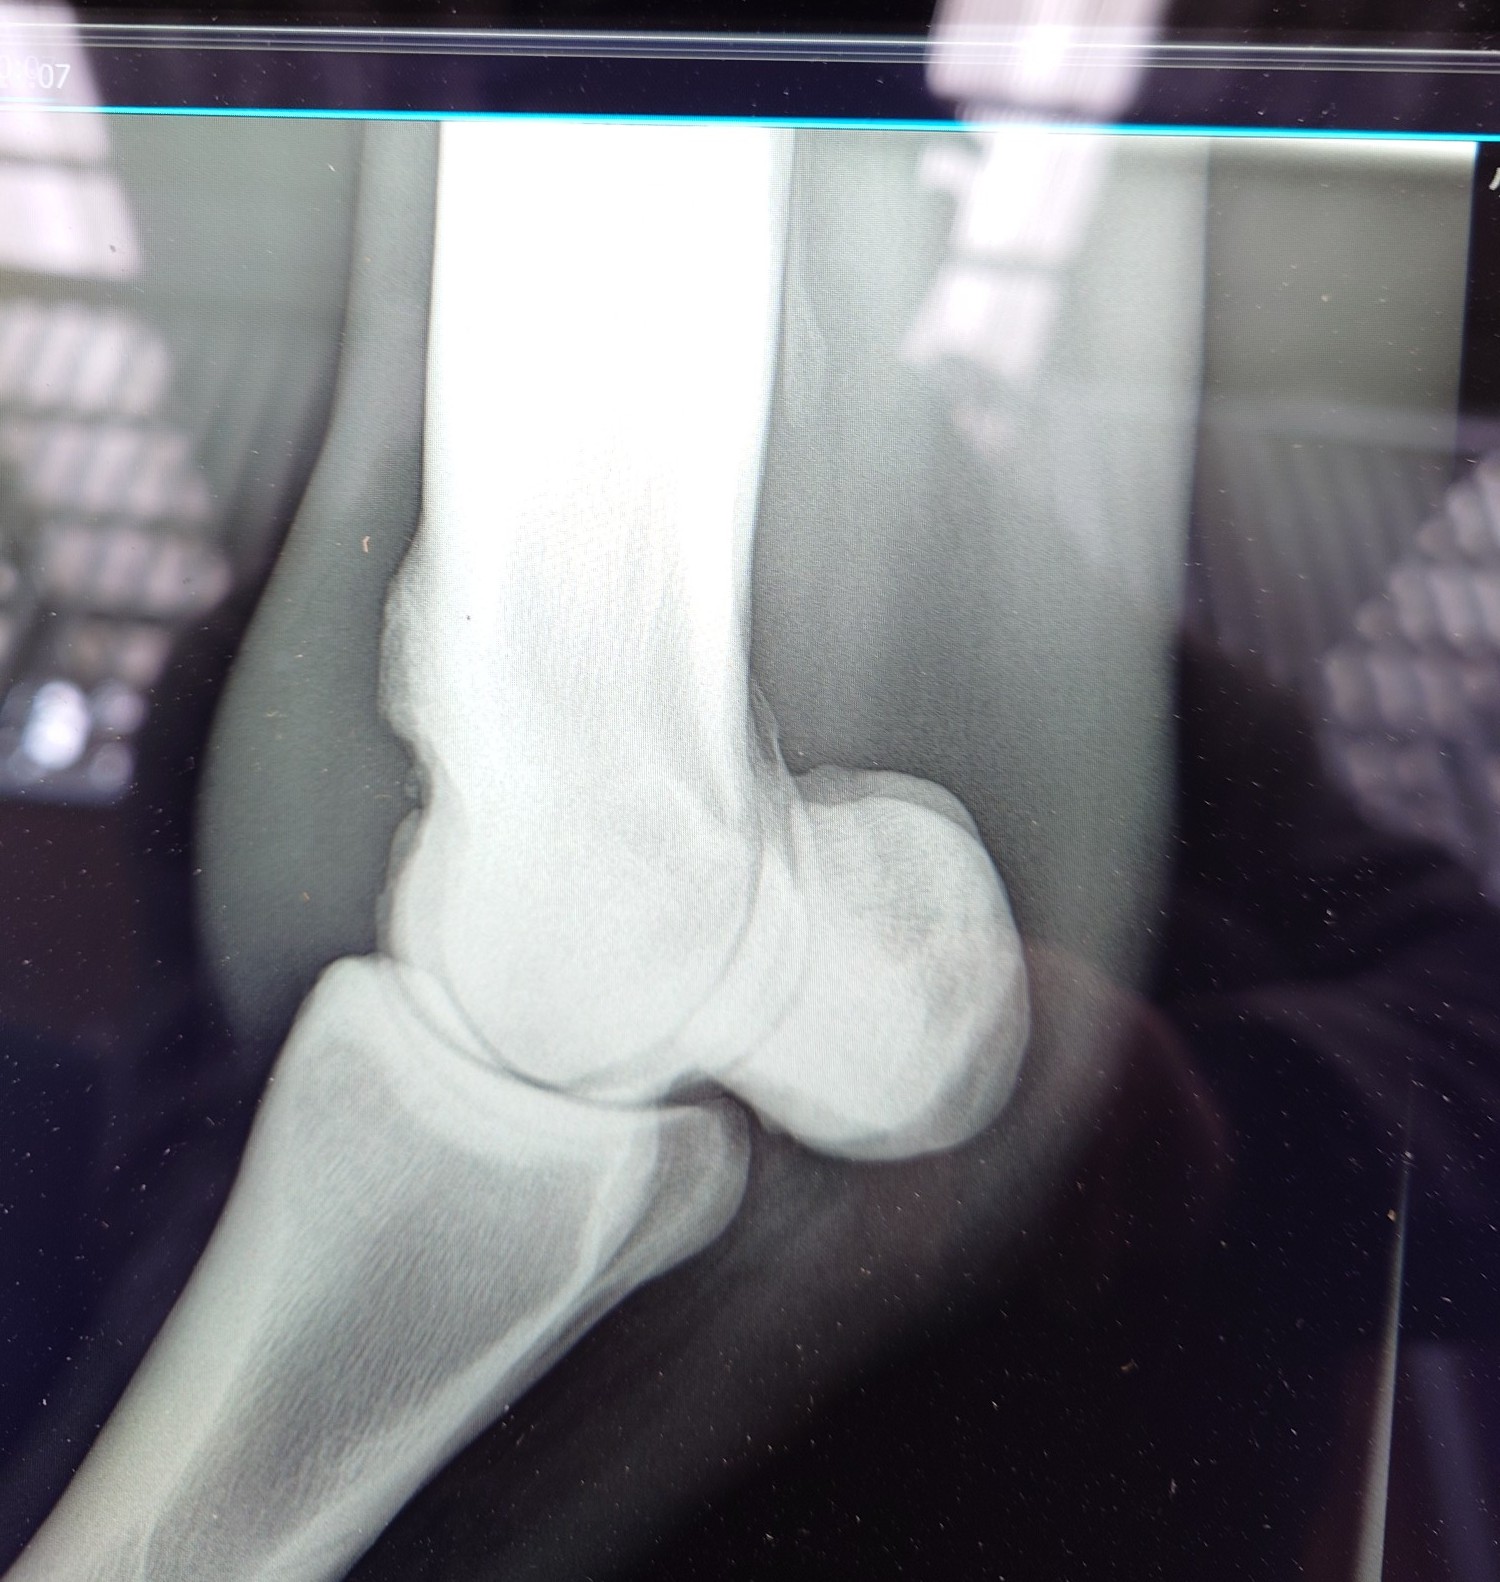

2012年にケンタッキーダービーを制した父アイルハヴアナザー産駒はアナザートゥルース(セン12歳)、オメガレインボー(牡10歳)他、タフなダート馬が多い。本馬は2歳時の6月に大井競馬場で新馬勝ちし、ハイセイコー記念6着後、3連勝で雲取賞へ臨み3着。羽田盃、東京ダービー後、休養して秋はA2B1クラスで出走しましたが惨敗が続いたため4歳時の2月28日に去勢。その後も結果を出せませんでしたが、5歳の8月にライアンクアトロ騎手が跨って快勝。そこからコンスタントに出走してA2(JRA交流2勝)クラスの特別戦で4勝を挙げました。8歳になった今年の3月の川崎戦で8着後、左前脚の球節が腫れてしまい、レントゲン検査で骨膜を発症していることが判明しました。剥がれかかっており、獣医師から全治3~4カ月と診断されたため現役を断念、引退することになりました。